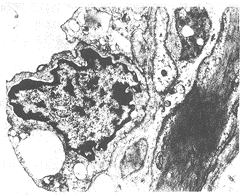

图2 伤后4小时可见血管内皮细胞(VEC)

肿胀,细胞间隙增宽〈↓〉,线粒体〈M〉

肿胀,空泡变。TEM×7000

复苏组伤后4h可见血管内皮细胞肿胀,细胞间隙增宽,线粒体肿胀空泡变(图2);伤后8h见内皮细胞膜完整性破坏,部分内皮细胞脱落(图3)。治疗组伤后4h可见内皮细胞膜结构完整,核膜清晰,线粒体肿胀,嵴突清晰(图4);伤后8h见核膜出现皱折,胞浆空泡变,线粒体肿胀(图5)。